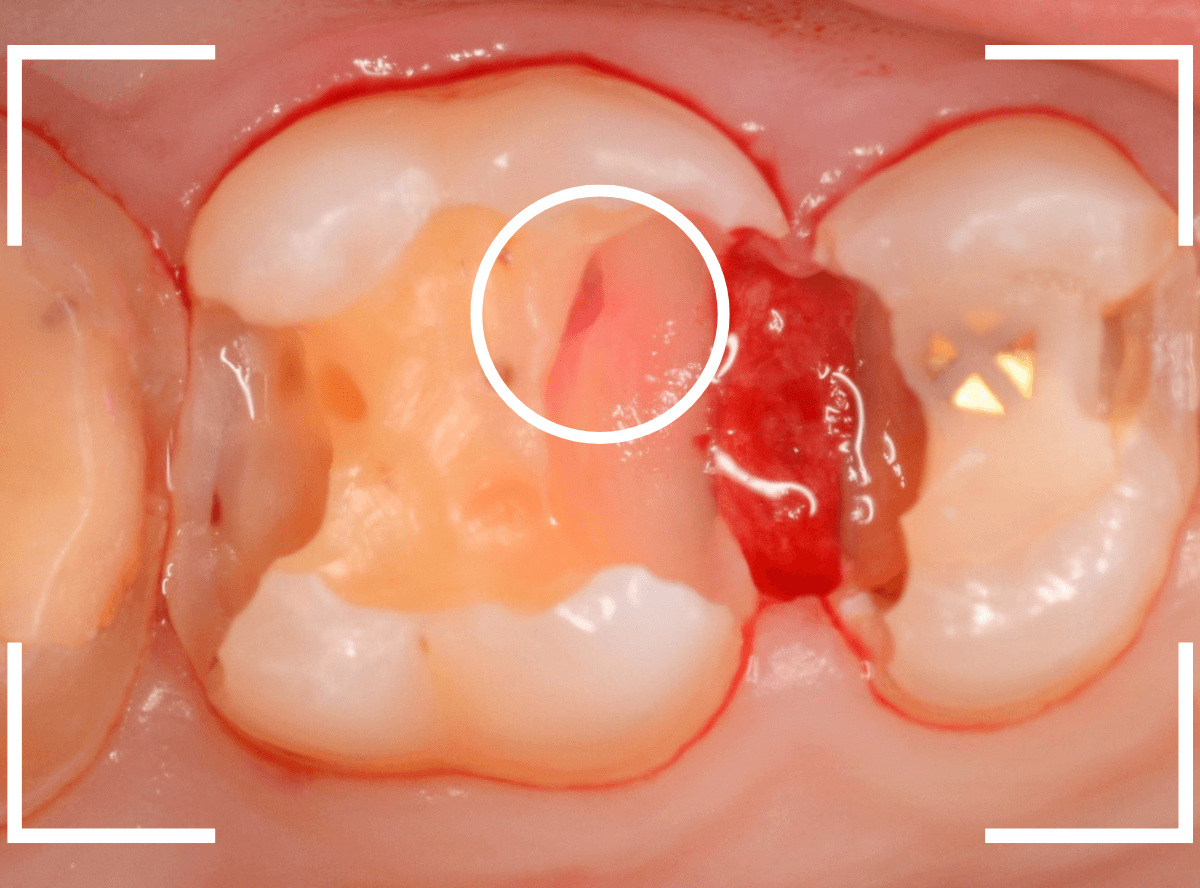

Case.11 外れたつめものの中は、ひどい虫歯

「上の奥歯のつめものが外れた」という訴えで来院された患者さんの例です。

つめものの外れてしまったつめものの中が虫歯になっているのが見えます。

レントゲン写真で確認します。

赤いラインが虫歯、青いラインが歯の神経です。

現在、つめてあるレジンの中まで虫歯が大きく進行し、ほぼ神経まで達しているのがわかります。

虫歯の治療を開始します。

奥につめてあるレジンも除去して中を確認します。

さらに慎重に虫歯を除去します。

手前の歯まで虫歯が進行しているのがわかります。

全ての虫歯を除去したところです。

薄皮一枚、神経ギリギリのところで虫歯を食い止められました。

しばらくは、お薬をつめて経過観察が必要です。

今回、つめものが外れてしまったのは、つめものの中が虫歯になったせいだと考えられます。

今回は、つめものが外れたのが受診のきっかけになったのが不幸中の幸いでした。